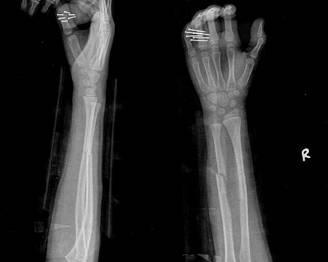

摘要:最新尺橈骨融合方法展現(xiàn)骨頭間的奇妙和諧與友情力量。通過(guò)先進(jìn)的醫(yī)療技術(shù),尺骨和橈骨之間的融合得到顯著改善。這種方法不僅提高了治療效果,還展現(xiàn)了人體骨骼之間的和諧關(guān)系。憑借友情和信念的力量,醫(yī)學(xué)界不斷突破,為患者帶來(lái)福音。

經(jīng)過(guò)醫(yī)生的診斷,小明被確診為尺橈骨融合,這是一種骨骼疾病,會(huì)導(dǎo)致尺骨和橈骨無(wú)法正常活動(dòng),聽(tīng)到這個(gè)消息后,小明和他的朋友們都感到有些緊張和害怕,但他們并沒(méi)有放棄,而是選擇相互鼓勵(lì),共同面對(duì)這個(gè)挑戰(zhàn)。

在醫(yī)生的介紹下,他們了解到了一種最新的尺橈骨融合治療方法——通過(guò)微創(chuàng)手術(shù)進(jìn)行骨骼融合的新技術(shù),這種方法不僅減少了手術(shù)風(fēng)險(xiǎn),還能更快地恢復(fù)活動(dòng)能力,雖然小明感到害怕,但他的朋友們一直陪伴在他身邊,給予他勇氣和力量。